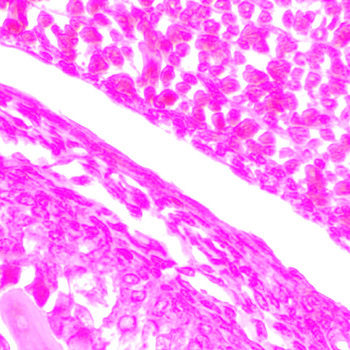

Retina Details (Choroid and Sclera)choroid is the vascular layer of the eye containing connective tissue and lying between the retina and the sclera. The sclera is the white part of the eye and protects the outer layer of the eye. Image of retina details prepared microscope slide at left was captured at 100x magnification. You can learn more about the retina here. |